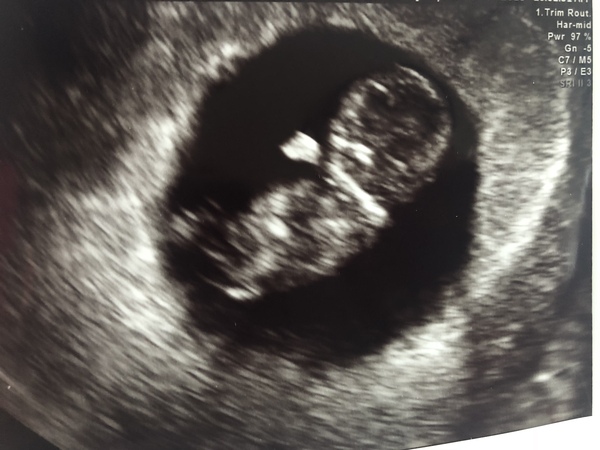

Had a lovely scan this morning, baby was very wiggly and could see hands and feet 😍 incredible the difference between 6 weeks and nearly 10 weeks. Here’s the little bean.

@MakeLemonade. What a great scan picture. It is amazing isn’t it to see them wiggly about x